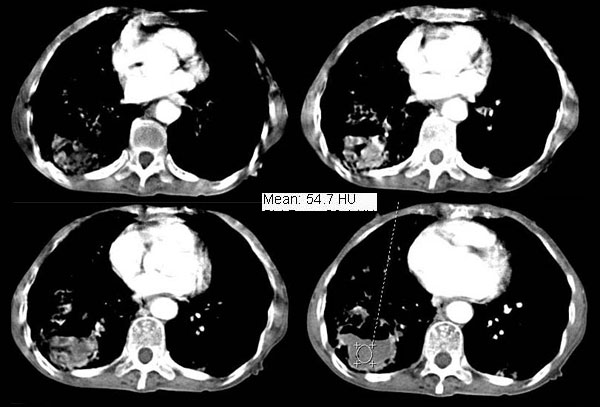

女:73岁;因一月前感冒后咳嗽,发烧,有大量脓痰,并且有恶臭味。

5毫米局部薄平扫

右肺下叶肺脓肿

补充_____伴双肺血行播散

右肺下叶示片状致密影密度不均,内见一空洞有宽液平,并可见壁结节周围示散在斑片模糊影,左下肺亦见一斑片模糊影,考虑 肺脓疡,肺癌不除外。

意见:1,右下肺脓肿;

2,双下叶支气管扩张;

右下肺脓肿,两下叶,中叶支扩并感染,右侧胸膜肥厚粘连。

该患者是我上个月作的,经正规抗炎治疗半月后平片显示吸收。{患者不愿ct复查}